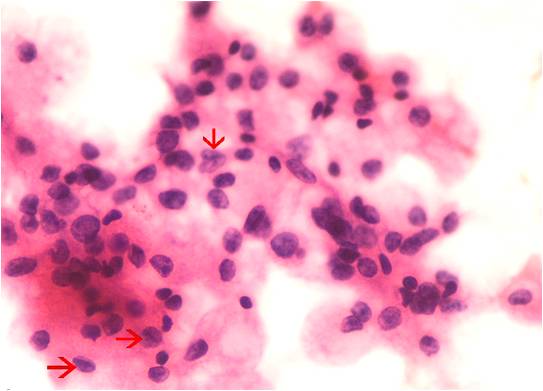

Background: Papillary thyroid carcinoma (PTC) is the most common among the thyroid malignancies. Fine needle aspiration cytology (FNAC) is the first line investigation in the diagnosis of thyroid lesions. Here we review the significance of certain features conventionally considered to be diagnostic of papillary thyroid carcinoma on FNAC – including type of background, type of colloid, presence or absence of papillary clusters, intranuclear inclusions and nuclear grooves which were also considered for their importance in early diagnosis of PTC.Methods: We reviewed all the thyroid FNACs performed over 18 months period and correlated them clinically and histopathologically, wherever available. Results: Out of a total of 354 cases of thyroid FNACs, histopathological correlation was possible in 90 cases, with a concordant diagnosis in 82 cases. Analysis of the 8 discordant FNAC smears revealed papillary clusters along with nuclear features, especially nuclear grooves to be the most important finding in indicating a diagnosis of PTC.Conclusion: Although the presence of papillary clusters along with characteristic nuclear features on FNAC is well known to indicate diagnosis of PTC, these findings can be easily missed on cytology smears, especially when the lesions are small (less than 1 cm) and diagnosis is clinically inapparent. Hence, we propose that the presence of papillary clusters in any case should alert the pathologist towards a diagnosis of PTC. A diligent search for nuclear features should follow. Thus a high index of suspicion while examining the FNAC smears in these patients will help in early detection of PTC.References